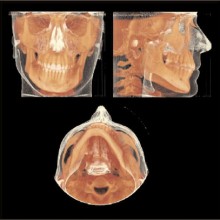

Each voxel is small (0.1-0.4 mm for each of the cube faces) and therefore the image has a relatively high resolution. The field of view can be adjusted to include a portion of or the entire maxillofacial region. The CBCT software allows for reformatting and viewing the image data from my point of view in straight or curved planes and in three-dimensions (Figure 1). Using these software tools the anatomy can be peeled away layer by layer to locate the desired anatomy. The CBCT ranks extremely high when considering the balance between high diagnostic yield, low cost, and low risk (Mah et al).

A tremendous amount of anatomic information is contained within the voxel volumes, and this information can be retrieved, analyzed, and viewed at a computer workstation using visualization and/or analytic software. The computer monitor is a two-dimensional, eight-bit display used to visualize three-dimensional, twelve-bit image data. The twelve-bit data can be viewed on an eight-bit display by using the technique of windowing, which allows for visualization of the entire 4096 shades of grey; eight bits at a time. Often, the anatomic volumes are acquired as voxel layers, and stacked as a series of parallel cross sections of the anatomy. These stacks can be displayed and viewed as a series of two-dimensional cross sections by sequentially paging through them in orthogonal planes (sagittal, axial, coronal). This is called multiplaner reformatting (MPR). MPR is the two-dimensional display of three-dimensional data in multiple projection planes (Figures 2a, 2b). Spatial relationships between three simultaneous displayed planes are communicated by projecting one plane onto the corresponding orthogonal planes as lines. Since the anatomic structures of interest occupy multiple layers within a stack, the clinician needs to perform a mental reconstruction of the anatomy. Coronal, sagittal, and axial views can be linked with synthesized views, such as oblique and/or curved slices or slabs. Slices or slab thickness can be manipulated directly and in real-time. The volume or slab of image data can be viewed with different modes of display, including MIP, SSR, and VR.

MAXIMUM INTENSITY PROJECTION (MIP) can be used to highlight features. The anatomic features associated with the brightest pixel or voxel intensity are projected on the display screen. This method creates a high-contrast image, but the brighter pixels/voxels may mask or superimpose over less-bright pixels, thus potentially hiding important anatomic features. MIP projections of a CBCT volume or slab (right or left sides) may be a useful method to produce constructed panoramic and cephalometric images for orthodontic purposes (Figure 3). Shaded surface Rendering (SSR) is useful for high-contrast imaging such as bone. SSR techniques allow the operator to set a pixel or voxel intensity threshold that excludes structures lower than the selected threshold, and renders all structures greater than the selected threshold (Figure 3). SSR creates a three-dimensional model that can be rotated as an object to be viewed from any angle. When the tissue contrast is not high, then the selected threshold may not perfectly render the desired anatomy. Volume rendering (VR) also creates a three-dimensional model using no